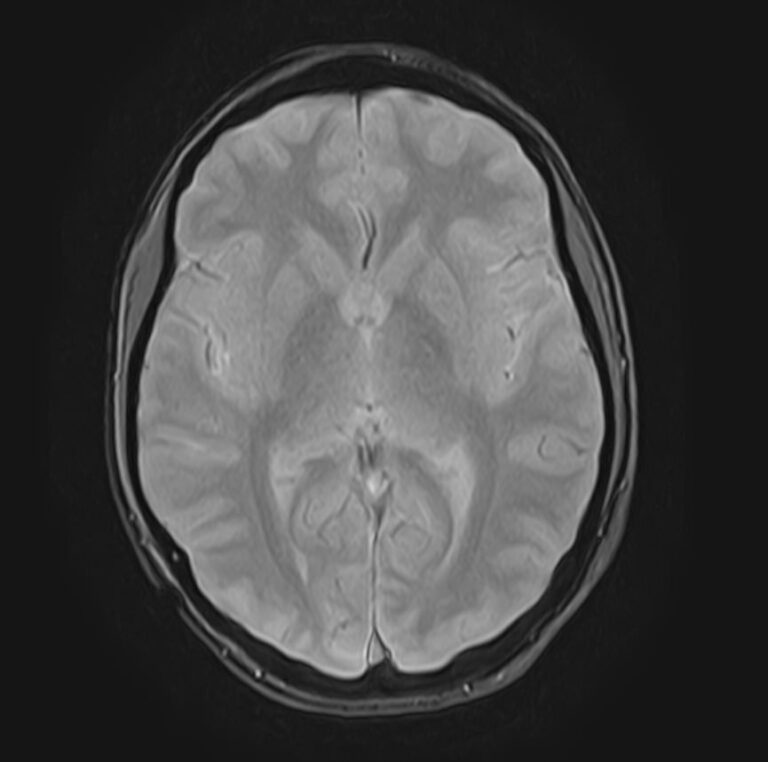

В клинике «Доступная медицина» можно пройти комплексное обследование, включающее в себя два протокола сканирования близко расположенных друг от друга анатомических областей – шейного отдела позвоночника и головного мозга. Метод комплексного обследования оценивает состояние всех структур головного мозга и самого верхнего сегмента позвоночного столба, который включает в себя 7 шейных позвонков, спинной мозг с отходящими от него нервными корешками и окружающими мягкими тканями.

Сканирование проводится на современном высокопольном магнитно-резонансном томографе закрытого типа TOSHIBA VANTAGE TITAN 1,5 Тесла. Магнитно-резонансный томограф производит послойное сканирование исследуемой зоны в разных плоскостях, затем при помощи компьютерных программ преобразует полученные данные в трехмерные изображения с высокой степенью детализации.

Что показывает МРТ головного мозга + шейного отдела позвоночника

В рамках проведения данного комплексного исследования можно выявить:

• очаги ишемического и геморрагического инсульта, область поражения, признаки отека головного мозга, стадию развития заболевания;

• доброкачественные и злокачественные новообразования, их точную локализацию, стадию развития процесса, проводить динамическое наблюдение за опухолевым процессом на фоне лечения;

• признаки демиелинизирующих заболеваний (рассеянный склероз), выявить очаги поражения миелиновой оболочки нервных волокон, определить стадию заболевания;

• характерные признаки дегенеративных заболеваний головного мозга (болезнь Альцгеймера, старческая деменция, болезнь Паркинсона), определить изменения коры головного мозга и подкорковых структур;

• поражение структур головного мозга на фоне травм, гематомы головного мозга;

• изменения, характерные для психических расстройств различного генеза (эндогенных и экзогенных), после вирусных инфекций, черепно-мозговых травм, отравлений токсическими веществами, на фоне наследственных заболеваний;